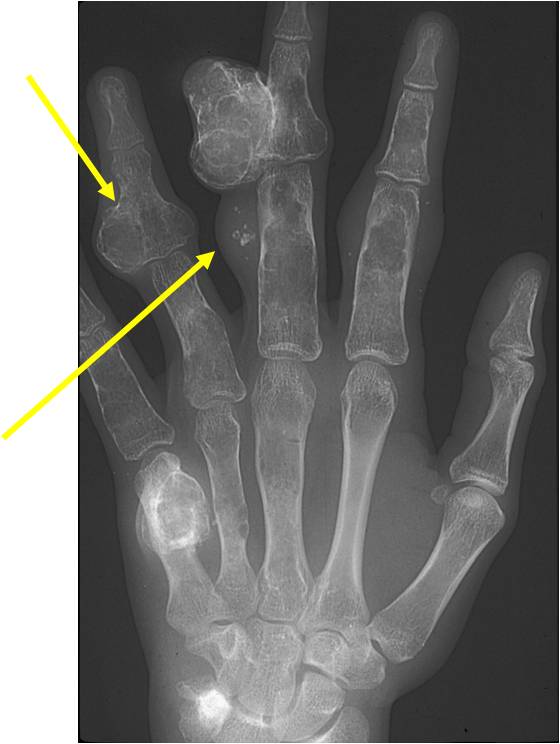

- Phleboliths (calcifications) usually seen in hemangiomas on X-ray

- Hands and feet greatest involvement

- Typical enchondromas

- Geographic IA-IIB with expansion

- Lytic columns from epiphyseal plate

- Chondroid matrix calcification

- Growth disturbance and bowing

- Maffucci: Soft tissue mass/hemangiomas with phleboliths